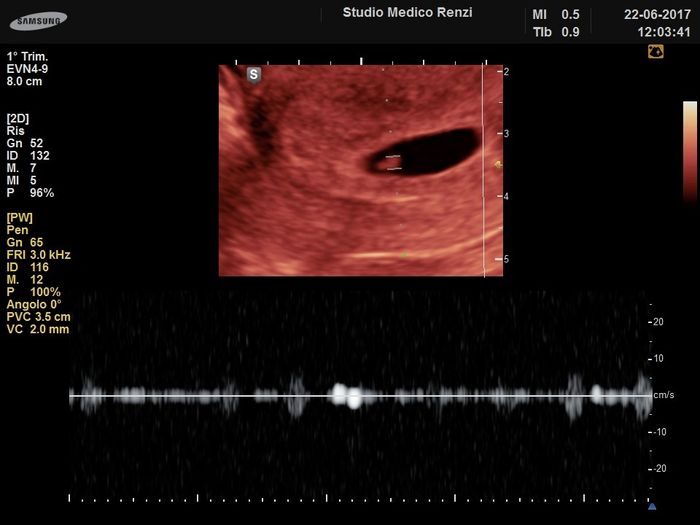

Io ho fatto l'eco a sette settimane e il doc mi disse che avevo ovulato una settimana in ritardo quindi ero di sei... Anche a me si è visto bene e sentito il battito ti lascio la foto... Ora sono a 28+5 quindi stai tranquilla!

Prima ecografia 3